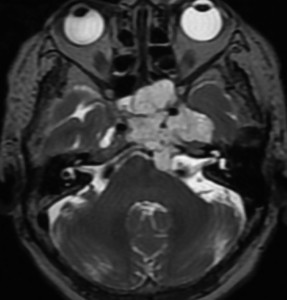

T2強調画像で高信号となるのは脊索腫と同様です。斜台後方の硬膜を破って前橋槽に伸展しています。これも脊索腫と同じような伸展浸潤形態と言えます。

骨軟骨腫が若い時からあって壮年になってから悪性化した軟骨肉腫です。20代のときに右外転神経麻痺が生じて20年以上そのまま経過しました。左のCTでは頭蓋骨の真ん中の斜台というところに異常な骨があって,良性の骨軟骨腫のように見えます。でも右側のMRIでは脳幹部に深く食い込む柔らかい腫瘍の部分が写っていてこれは軟骨肉腫を疑う像です。手術摘出と術後の放射線治療をしました。